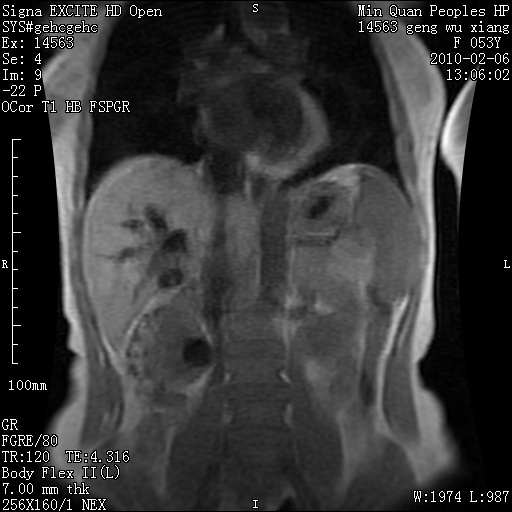

标题: MRI2762:胆道梗阻原因?

f,53y,全身黄染多日。

高位胆道梗阻 胆管癌可能性大

支持 高位胆道梗阻 胆管癌可能性大。